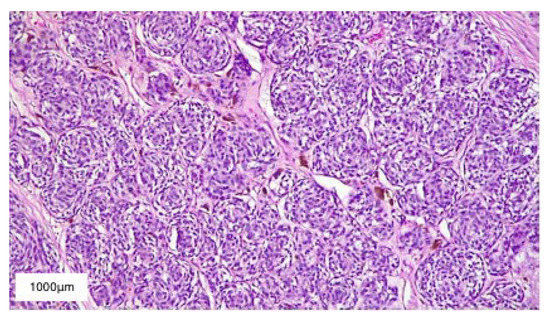

2. Case Presentation